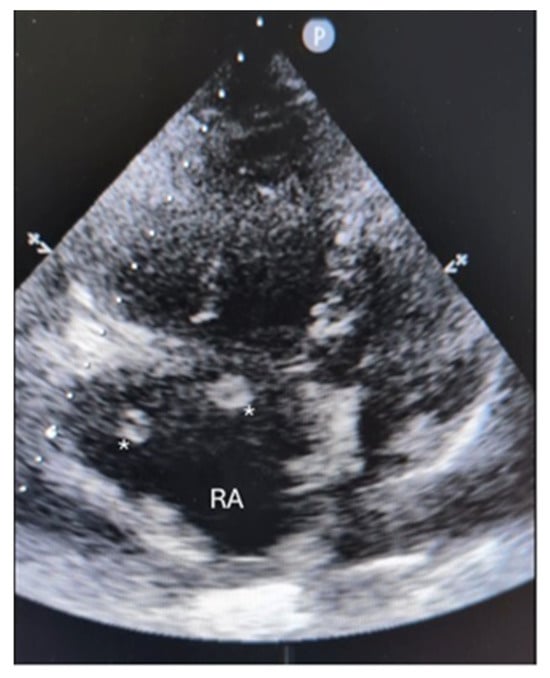

图2. 即时超声检查(POCUS)显示右心房(RA)内有一个较大的蛇形血栓(用星号*标注),该血栓通过三尖瓣脱垂进入右心室,符合移动性血栓的特征。POCUS还显示右心室功能障碍,TAPSE值为8毫米,下腔静脉扩张,支持阻塞性休克的诊断。尽管CTPA仍是诊断肺栓塞的标准化影像学方法,但在心动过速和呼吸困难的患者中,由于运动伪影的影响,CTPA可能无法检测到心内血栓,尤其是在未使用心电图同步触发进行扫描的情况下,CTPA对移动性血栓的阳性预测值约为57%[

2]。因此,POCUS越来越多地用于诊断移动性血栓,并识别与急性肺栓塞相关的病理变化,如右心负荷过重[

3]。在急性肺栓塞患者中,POCUS的检出率为4%[

4]。对于需要紧急治疗的病例,POCUS对于及时临床决策至关重要,因为这些病例可能无法通过标准影像学方法检测到[

5。